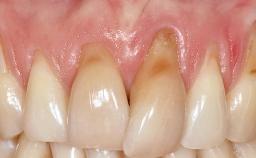

A 30-year-old woman was referred by her general dentist for evaluation of an esthetic complication related to previous implant treatment for congenitally missing maxillary lateral incisors. The patient’s chief complaint was the inadequate esthetic appearance of her smile. The case demonstrates the use of a combined approach to achieve optimal results. Two different flap designs - a tunnel technique and a coronally advanced flap - are employed based on the surgical objectives for the affected site.